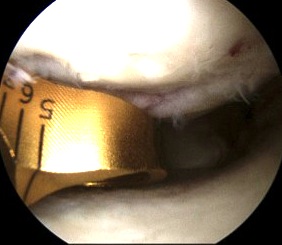

3. All inside

Instruments

- meniscal arrows (Biostinger, Meniscus Arrow)

- meniscal screws

- meniscal suture anchors (FasT-Fix, RapidLoc)

Technique FasT - Fix

- ipsilateral portal to view

- contralateral portal for instruments

- 2 x absorbable sutures anchors posteriorly

- may have to change portals for mensical body sutures

- pass first bioabsorbable anchors through meniscus and capsule

- retract and advance second anchor

- place anchor through meniscus (horizontal) or into capsule alone (vertical)

- advance knot, cut